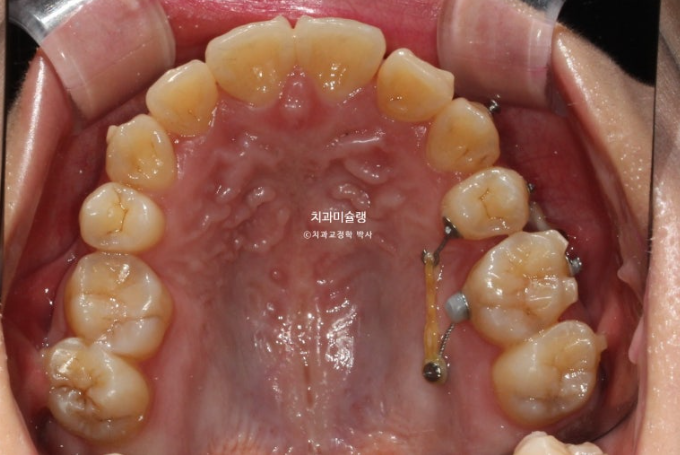

23년 10월 교정치료를 이해 온 30대 환자분입니다.

약 2mm 정도의 중심선 불일치 그리고 덧니가 보입니다.

개방교합도 있고

30년간 공간이 없어서 미처 내려오지 못한 작은어금니도 있습니다.

덧니가 워낙 심해 작은어금니 4개 발치가 불가피한 상황입니다.